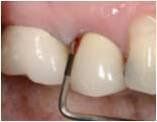

- Allungamento di corona

- Endodonzia